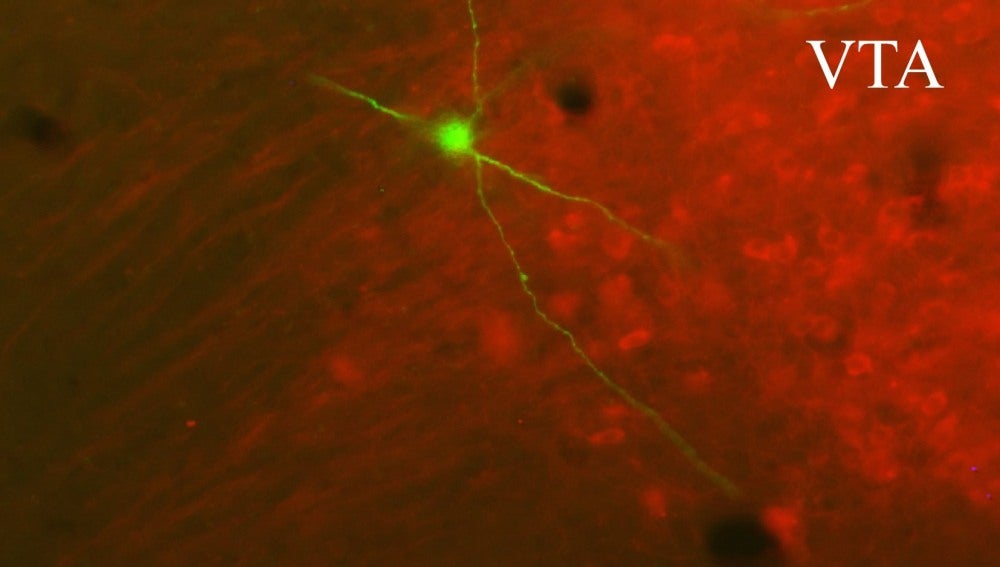

El área tegmental ventral (VTA) es el principal eslabón del denominado “circuito de recompensa cerebral”. Esta área contiene neuronas que se proyectan hacia numerosas regiones del cerebro, desempeñando un papel fundamental en la motivación, el deseo, el placer y la valoración afectiva.

Los cuerpos de las neuronas de la VTA se sitúan en el tronco encefálico. Los axones de estas neuronas –prolongaciones especializadas en conducir el impulso nervioso desde el cuerpo celular (soma) hacia otra célula­– liberan dopamina, inervando con este neurotransmisor la corteza cerebral y otras regiones cerebrales.

En el trabajo, los investigadores emplearon una técnica novedosa de transfección in vivo de neuronas individuales que les permitió visualizar y cuantificar el axón completo de una sola célula, sin importar la extensión y complejidad del axón.

“Los circuitos del cerebro están formados en gran parte por neuronas cuyo axón se extiende y ramifica sobre distancias enormes, de decenas de centímetros en el caso del cerebro humano. Hasta ahora había sido imposible analizar esos circuitos con resolución celular. Es el sueño de Santiago Ramón y Cajal hecho realidad”, subraya Francisco Clascá, del mismo departamento.